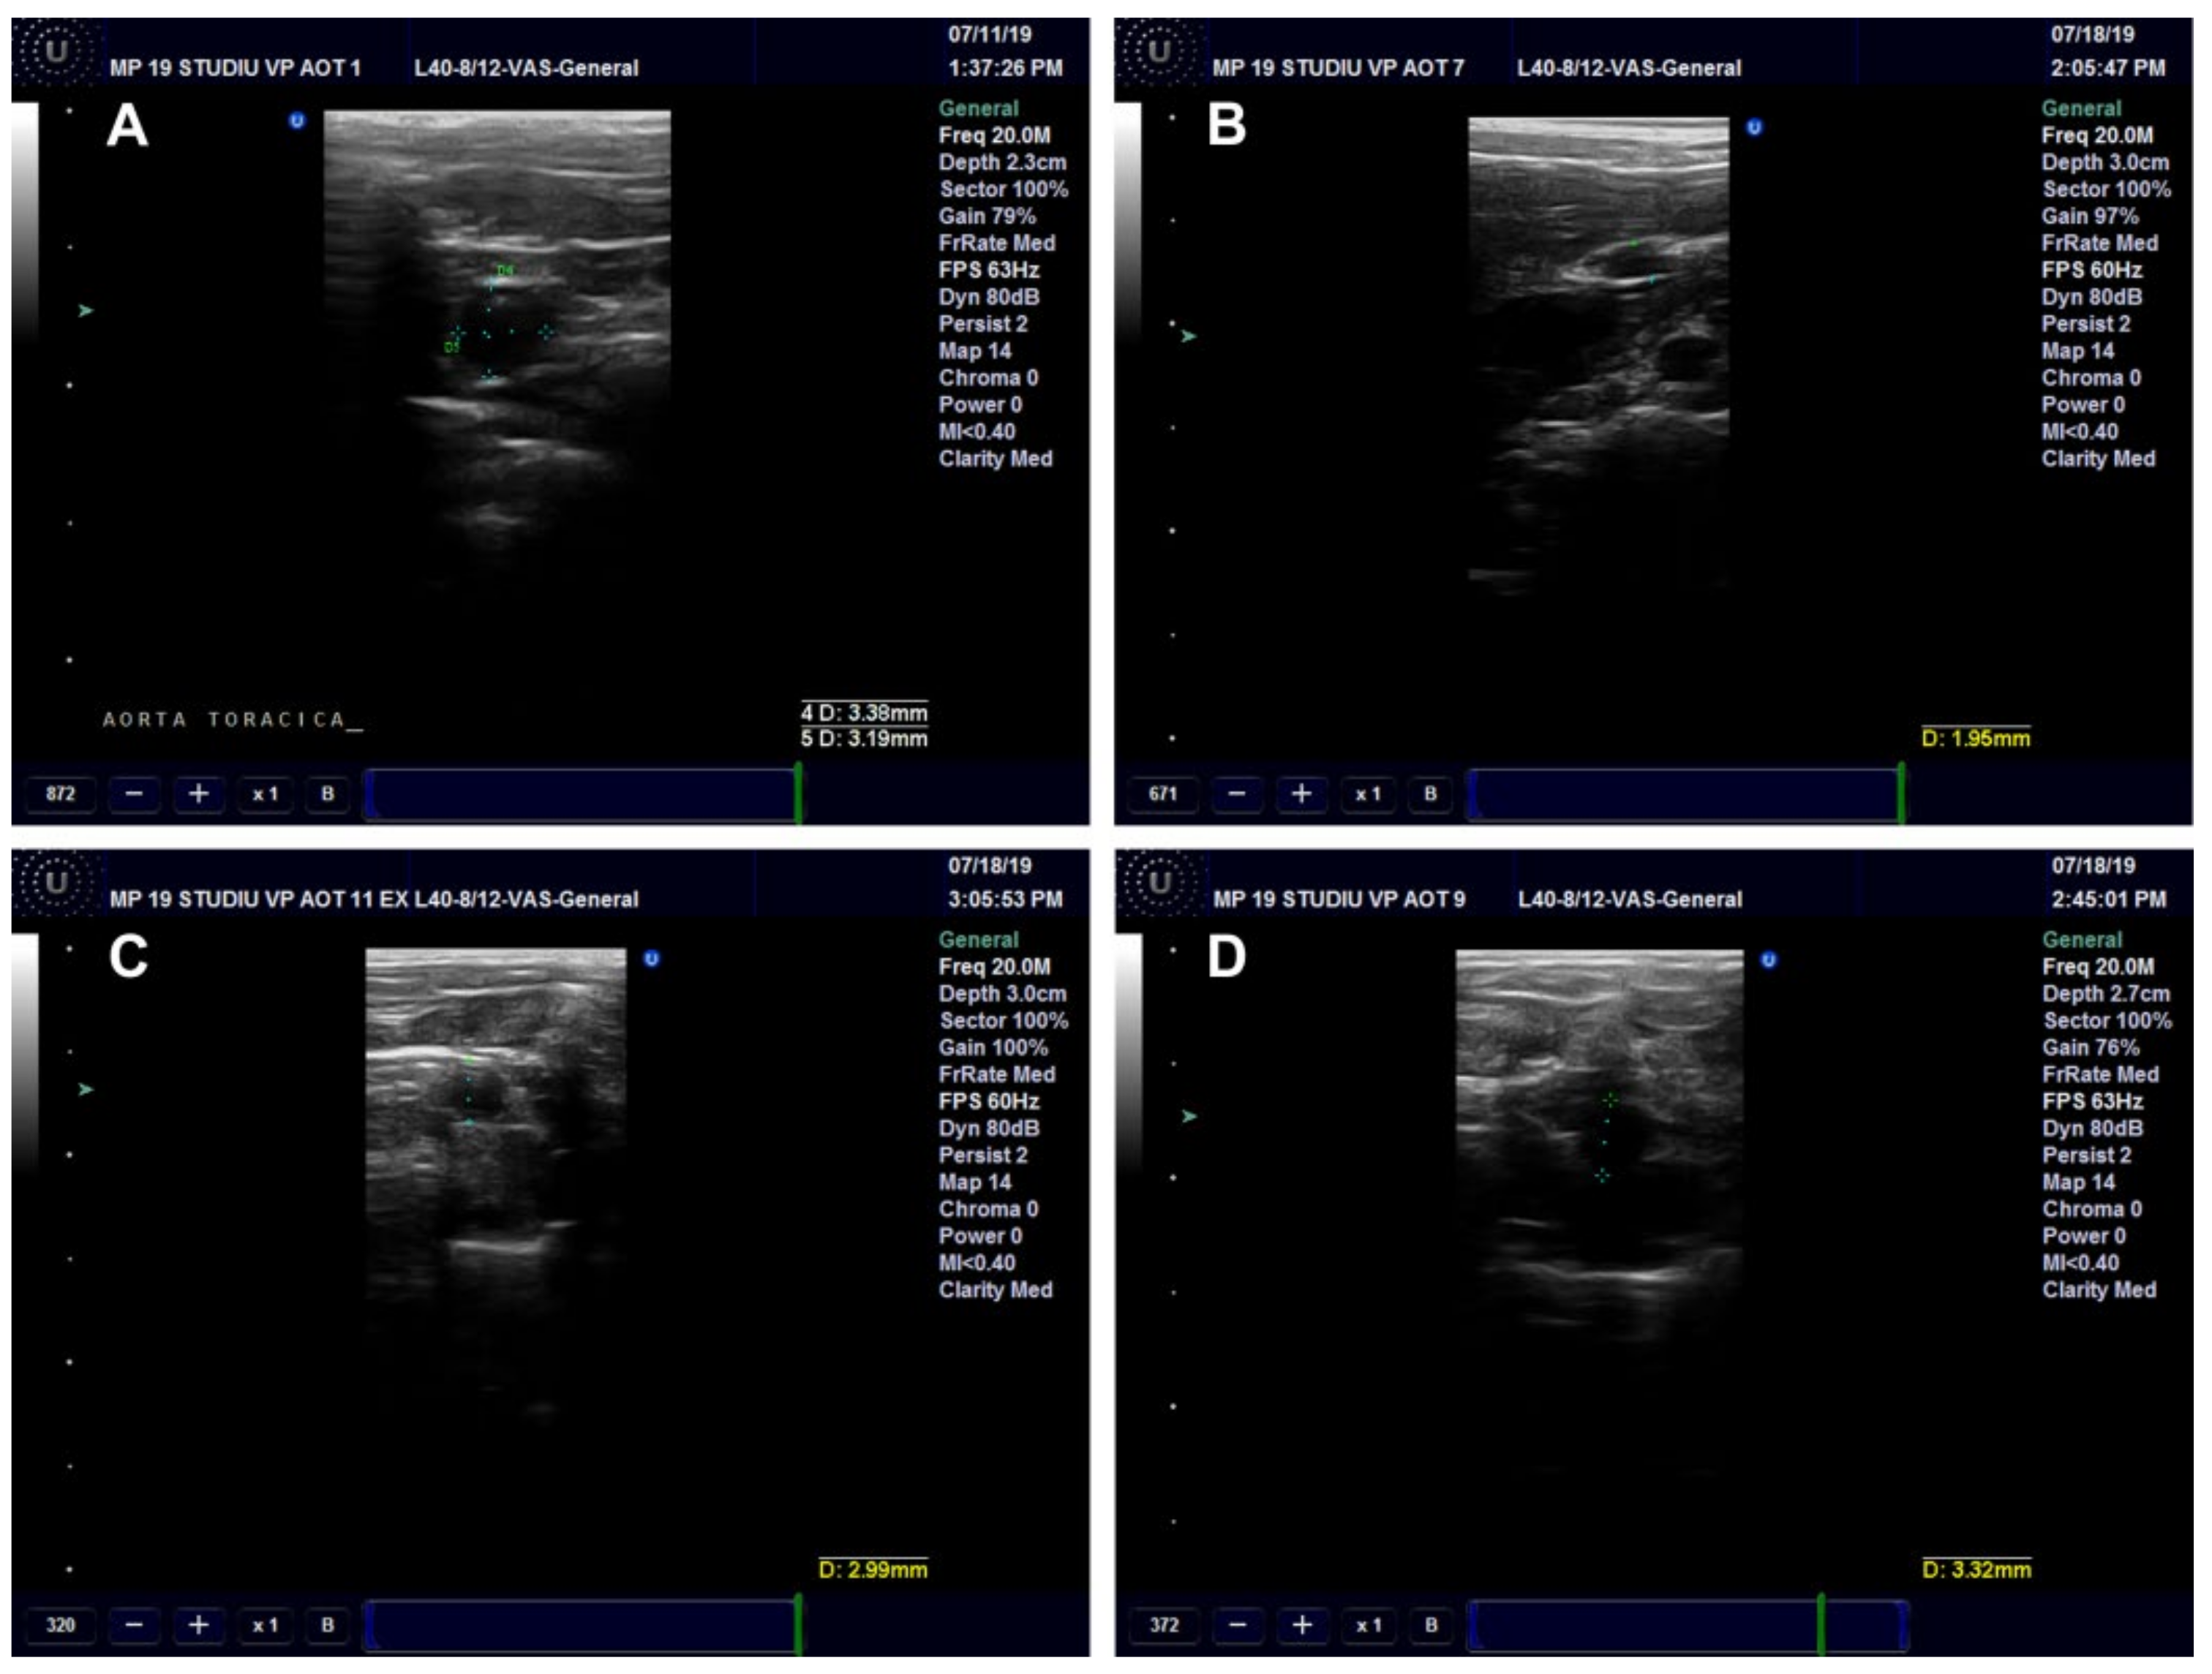

Ultrasound Examination of the Aorta and Left Ventricle